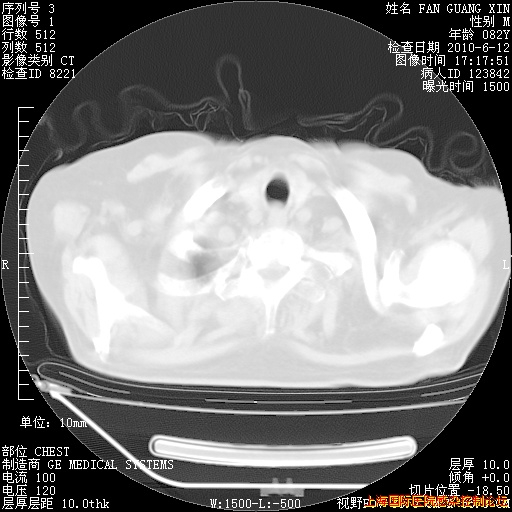

6月12日纵膈窗

整整相隔30天的肺部CT好像有所好转啊。甲强龙减量第3天,需要观察体温。

海管,自昨日你和我通完话后,不知您岳父消化道症状有无缓解?体温怎样?阅读7.12日胸部ct,个人认为目前激素治疗是有效的,甲强龙减量是适宜的。因在抗痨治疗,需密切观察肝功、肾功能和血常规。不过,老年、长期住院和大量使用激素,很担心菌群失调发生